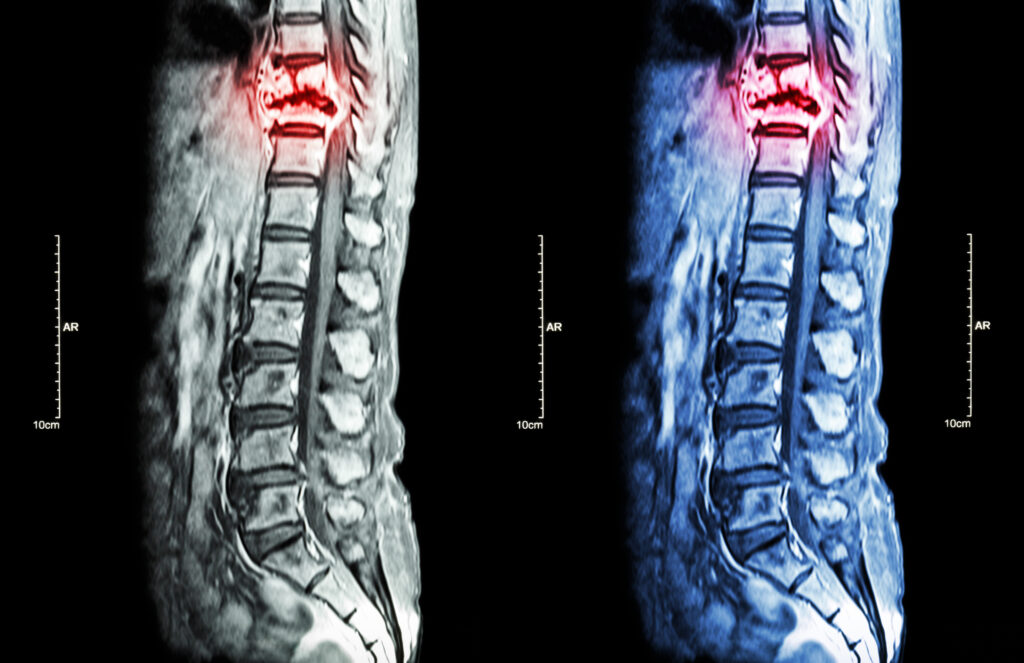

The spinal cord is the body’s communication highway, transmitting signals between the brain and the rest of the body. Damage from a car accident can lead to partial or complete loss of movement, sensation, or organ function.

Common Crash-Related Spinal Injuries

- Fractured vertebrae from rollover crashes

- Herniated or bulging discs due to rear-end collisions

- Whiplash leading to spinal cord swelling

- Direct trauma from high-impact crashes